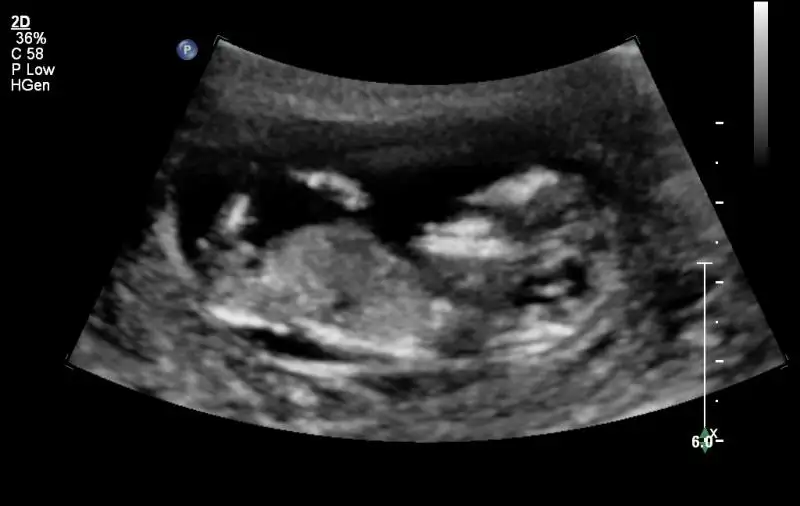

bak benim ufaklığın fotosu teyzesi yok işte pipimizya bize de 16. haftada daha net bir şey söylerim dedi zaten ama nedense bana emin gibi geldi doktor

12 haftalık hamsi heee alemsin yaaa yan yatmış nerden görücem varsada sen gene umutlanma annesi heran herşey değişebilirben bu konuya çok takmıyor sonuç çok önemli değil ilk bebeğimiz sonuçta ikisindende yokki o olsun bu olsun diyeyim

Bebek çok hareketli dedi. Kese aşağıya inmemiş düşük gibi gözükmüyor dedi. Çok sağlıklı bir bebek dedi hatta. Kanama olup etkilenmemesi ilgiçmişÇok hareket ettiğinden cinsiyeti tam olarak göremedik yine. Normalde ikili testi bugün olacaktık ama kanama olduğu için cumartesi gününe tekrar randevu verdi. Ayrıca anneme 1 hafta rapor verip tuvalet dışında kalkma dedi. Bende şikayet ettim annemi beni dinlemiyor diye Velhasıl kardeşim çook iyi gözüküyor. Çoook hareketli eli ayağı hiç durmuyor hatta :) Çok mutlu oldum yaaa. kalbide pıt pıt atıyor. Kendi çocuğum olsa bundan heyecanlı olmazdım heralde